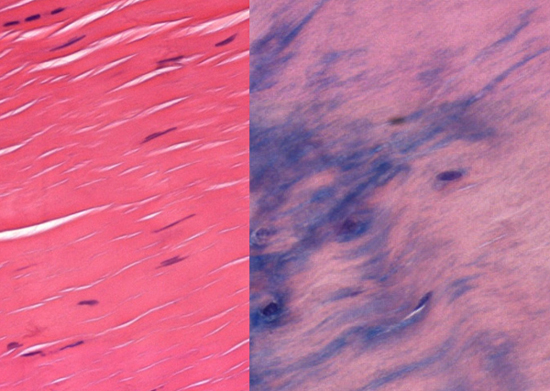

Searching for Better Treatments for Irritated TendonsResearchers learn what makes tendons fray in old age, knowledge that could help develop better treatments for tendinosis and regrow damaged tissue. When tendons get irritated it can lead to a serious condition called tendinosis—a common class of sports and workplace injuries—which is also common in older individuals. It can take many weeks of rest for tendon irritation to heal, with no treatments, save short-term steroid injections and surgery, followed by more rest. New research on the biology of tendon irritation from Jefferson (Philadelphia University + Thomas Jefferson University) pinpoints key molecular components of injury, opening the possibility of targeting the pathways with pharmaceutical and other interventions. “The most effective natural method for treating tendinosis is to stop the repetitive action that causes the injury in order to let the area heal,” says surgeon and cell biologist Rowena McBeath, MD, PhD, at the Philadelphia Hand to Shoulder Center at Jefferson Health, who led the study. “But stopping an activity that people depend on for income can be quite difficult. Patients often get worse and ultimately require surgery and even lengthier recovery periods.” Other research has shown that tendon cells change shape under compressive forces, becoming tougher and more like the cartilage in the knee meniscus. Research also suggested that as people age the blood supply to tendons decreases, leaving them starved of oxygen. “Our analysis links these two avenues of research, showing that decreased oxygen is a key event that leads tendon cells to go from healthy to tougher and less flexible, resulting in tendinosis,” says McBeath. The results were published in the journal Aging Cell. McBeath and colleagues examined tendon samples from patients who were undergoing surgery for tendinosis and compared tendons from elderly vs young patients. Under normal oxygen levels, the tendon cells retained a normal shape and flexibility. But when those cells were grown in low-oxygen levels, mimicking the low-oxygen environment common in older people, the tendon cells changed shape, and became round and more similar to tough cartilagelike cells, called fibrocartilage. When oxygen was low, the aged tendon cells also reduced the activity of a signaling molecule called Rac1. Rac1 is involved in many cellular processes, including those governing cell shape, movement and growth. With reduced Rac1, the tendon cells began to change shape, but only in low-oxygen conditions. When the researchers blocked Rac1 activity in high-oxygen conditions, tendon cells were able to retain their normal shape.